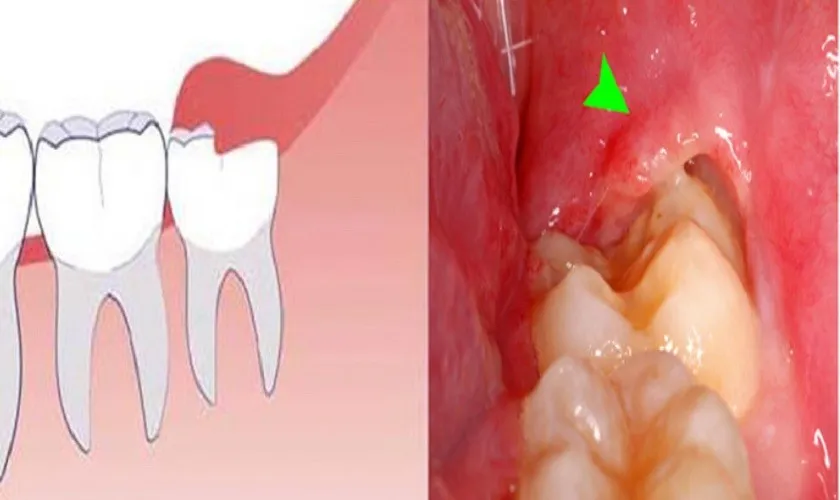

Mọc lệch, mọc ngầm hoặc nằm dưới nướu gây đau, viêm tái phát thường xuyên

Khi răng khôn mọc lệch, nó không chỉ gây ra cảm giác đau nhức mà còn làm tổn thương đến các răng xung quanh. Điều này xảy ra do áp lực từ răng khôn có thể đè lên răng số 7, dẫn đến tình trạng xô lệch và hình thành khe giắt thức ăn. Với tình trạng này, việc vệ sinh răng miệng trở nên khó khăn hơn, tạo điều kiện cho vi khuẩn phát triển, gây ra tình trạng viêm nhiễm.

Khi răng khôn nằm ngầm dưới nướu, không thể mọc lên, nó có thể tạo ra áp lực đến chân răng, gây viêm nhiễm lợi và đau đớn cho bệnh nhân. Những triệu chứng như sưng nướu, đau nhức và khó chịu có thể tái phát nhiều lần, gây ảnh hưởng đáng kể đến chất lượng cuộc sống của người bệnh. Nếu để lâu, tình trạng này có thể dẫn đến viêm xương hàm và các biến chứng nghiêm trọng khác.

Răng khôn chèn ép răng số 7 hoặc gây xô lệch hàm, có khe giắt thức ăn

Răng khôn mọc không đúng vị trí rất dễ gây chèn ép lên các răng bên cạnh, đặc biệt là răng số 7. Hệ quả kéo theo là răng số 7 có thể bị xô lệch, gây ra hiện tượng đau buốt mỗi khi nhai thức ăn. Nếu tình trạng này kéo dài, có thể gây ra một loạt các vấn đề khác như viêm nhiễm nướu, sâu răng và thậm chí dẫn đến mất răng.

Sự hình thành khe giắt thức ăn giữa răng khôn và răng số 7 là một yếu tố quan trọng khiến việc vệ sinh răng miệng gặp khó khăn. Thức ăn dễ bị mắc kẹt tại các vị trí này, tạo nên môi trường thuận lợi cho vi khuẩn sinh sản, từ đó gây ra các bệnh lý về răng miệng. Việc tích tụ mảng bám quanh răng khôn sẽ dẫn đến sâu răng, viêm nướu và thậm chí làm tổn thương đến chân răng.